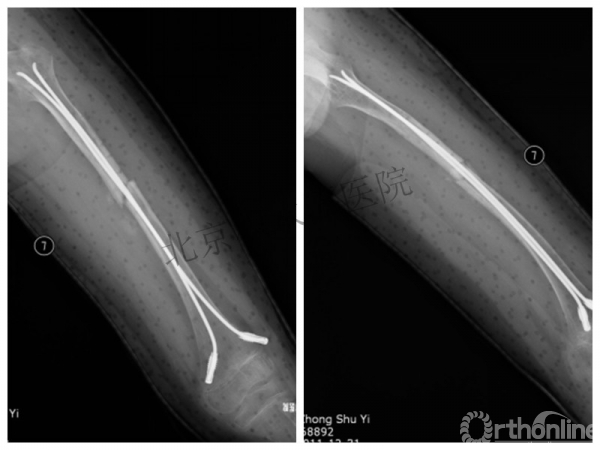

男孩、9岁,滑雪受伤,胫腓骨螺旋形骨折(粉碎性)

这个病例郭教授在积水潭医院骨科高研班时多次讲到,也在互动交流中惊人地看到,了解到现实之令人难以想象!

手法整复,石膏制动!

整复后7天

儿童具备强大的愈合潜力,同样也有极强的塑形能力

某种情况下,The best treatment is no treatment! 最佳治疗反而是不治疗!因为很多骨折依靠儿童强大的塑形能力和特点完全可以得到满意的结果!